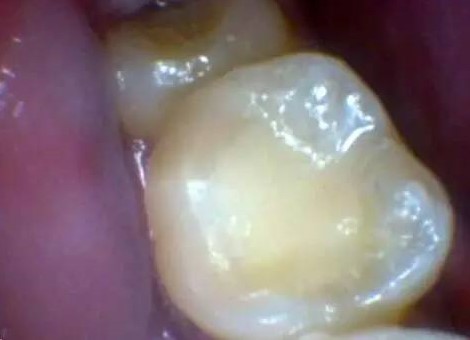

补完后的样子。

牙齿的问题真的是需要预防,早发现,早治疗,越拖问题越大!现在就拿起镜子,照照你的后牙,看是否有窝沟龋吧!